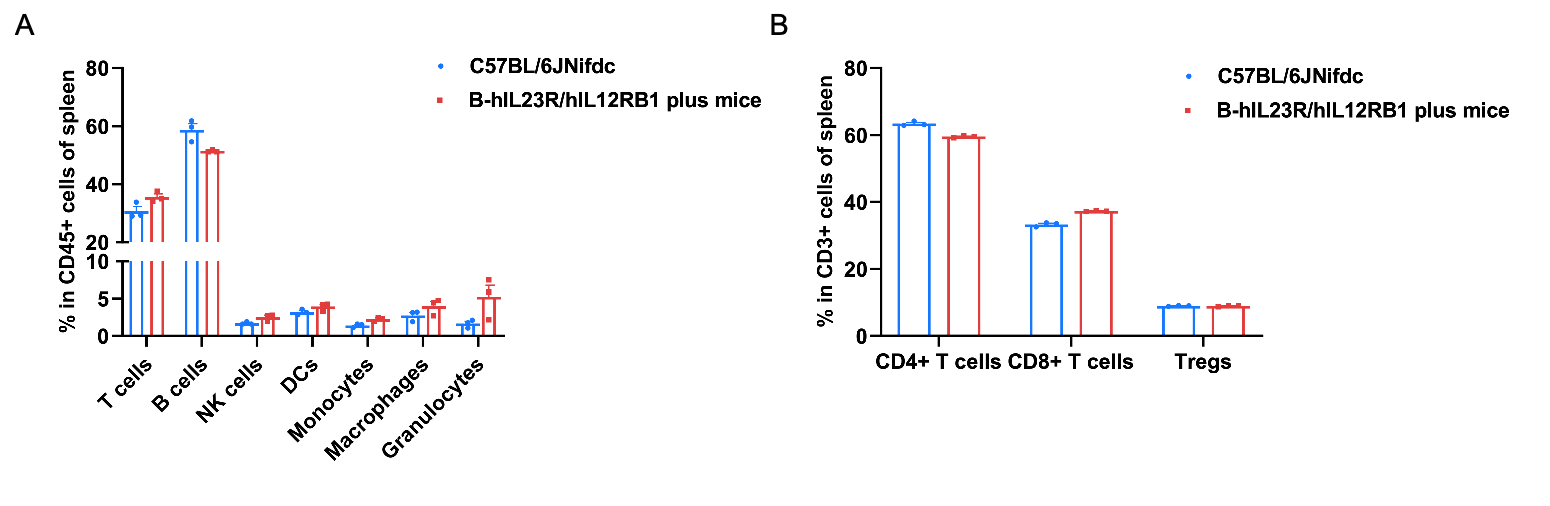

Frequency of leukocyte subpopulations in spleen by flow cytometry. Splenocytes were isolated from wild-type C57BL/6JNifdc mice (male, n=3, 6-week-old) and homozygous B-hIL23R/hIL12RB1 plus mice (male, n=3, 6-week-old). A. Flow cytometry analysis of the splenocytes was performed to assess the frequency of leukocyte subpopulations. B. Frequency of T cell subpopulations. Frequencies of T cells, B cells, NK cells, DCs, granulocytes, monocytes, macrophages, CD4+ T cells, CD8+ T cells and Tregs in B-hIL23R/hIL12RB1 plus mice were similar to those in C57BL/6JNifdc mice, demonstrating that humanization of IL23R and IL12RB1 does not change the frequency or distribution of these cell types in spleen. The frequency of leukocyte subpopulations in lymph nodes and blood of B-hIL23R/hIL12RB1 plus mice were also comparable to wild-type C57BL/6JNifdc mice (Data not shown). Values are expressed as mean ± SEM.